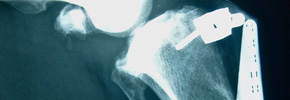

Kreuzbandriss beim Hund

Anders als beim Menschen reißt das vordere Kreuzband beim Hund meistens ohne ein Trauma._Degenerative Veränderungen und chronische Überlastung sind beim Hund die häufigsten Ursachen. Ein gerissenes Kreuzband muss beim Hund operativ versorgt werden (Extrakapsulärer Bandersatz oder TTA).

Kreuzbandriss/TTA Nachsorgeprotokoll